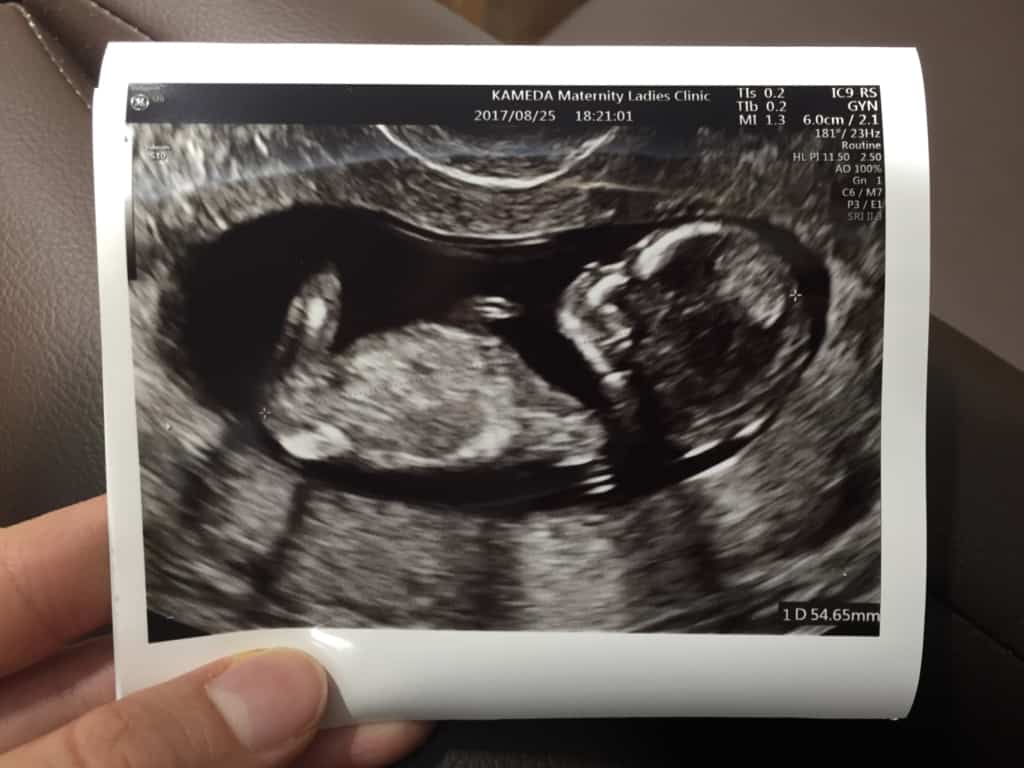

So, it's been a long while since I last posted here. During that time I went on my honeymoon, came back, got back to work, and celebrated my 28th birthday. And the photo above would explain why I haven't been actively blogging...

I'm pregnant! Tristan and I are expecting a little foodie baby in 2018!